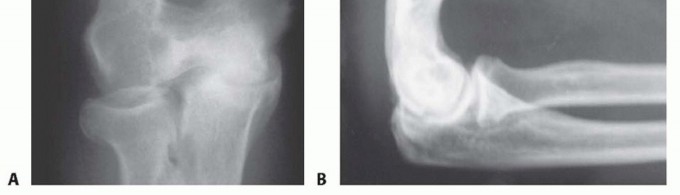

A review of the literature shows satisfactory results in over 80% of patients with open or arthroscopic technique.1,3,4,6,8,9,10,11,12,13,14,15,16,17,18,19,20Satisfactory pain relief is achieved in about 90% of patients with both techniques.1,3,4,6,8,9,10,11,12,13,14,15,16,17,18,19,20Extension improves by about 10 to 15 degrees, and flexion improves by about 10 degrees. Overall improvement in the motion arc is about 20 to 25 degrees (FIG 3).Comparative studies between the open and arthroscopic techniques demonstrated no statisticallysignificant difference in overall effectiveness.3,4 Higher gain in elbow flexion was achieved with the open procedure likely due to more extensive posterior débridement. Greater pain relief was achieved with the arthroscopic procedure, likely due to decreased scar formation.Therefore, arthroscopic technique may be considered in patients with moderate pain and arthritic changes in the anterior compartment of the elbow, whereas open ulnohumeral arthroplasty is preferred when advanced arthritic changes are present in both compartments of the joint.There have been no reports of postoperative instability.

FIG 3 • AP and lateral radiographs after ulnohumeral arthroplasty has been performed. The foraminectomy in the distal humerus can be easily seen. There are no osteophytes of the olecranon and coronoid process and the patient has gained a much better arc of motion without pain. Heterotopic ossification with limited elbow motion has been described in one report after openulnohumeral arthroplasty with a triceps splitting approach.2 However, development of heterotopic ossification without limitation in motion has also been reported in some cases after arthroscopictechnique.16Improper placement of the foraminectomy may result in a column fracture. Also, a fracture may occur if maximum loading is applied immediately postoperatively due to weakening of the columns of the distalhumerus.5